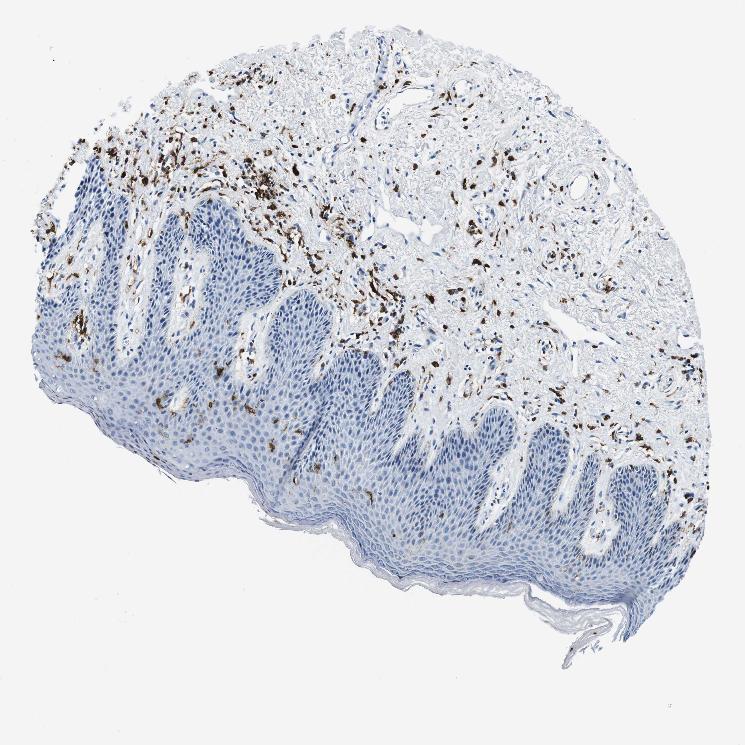

SKIN 2 - Antibody stainingi

Antibody staining in the annotated cell types in the current human tissue is reported as not detected, low, medium, or high, based on conventional immunohistochemistry profiling in selected tissues. This score is based on the combination of the staining intensity and fraction of stained cells.

Each image is clickable and will lead to virtual microscopy that enables deeper exploration of all samples and also displays staining intensity scores, fraction scores and subcellular localization as well as patient and tissue information for each sample.

Antibody HPA043151Antibody CAB015400Antibody CAB034021

Epidermal cells Not detectedNot detectedNot detected